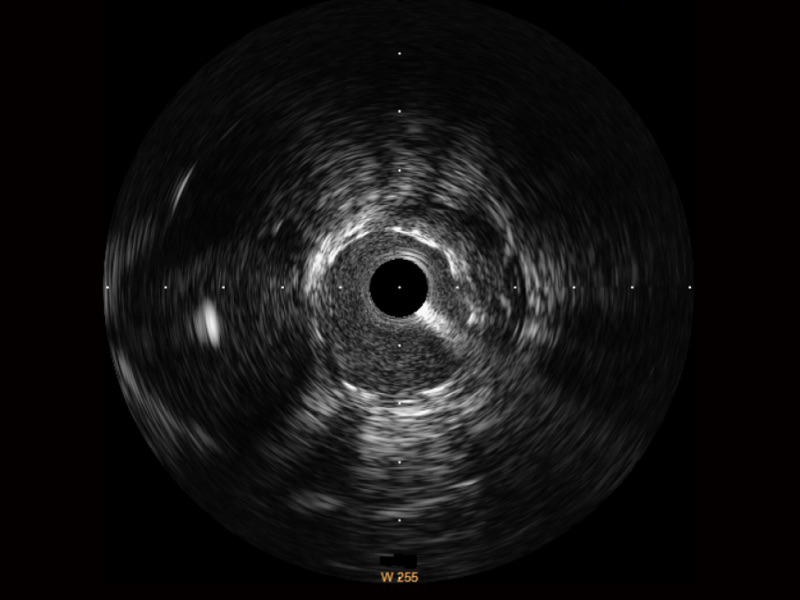

db真人体育官网宽频IVUS图像

传统IVUS图像

对比传统IVUS导管成像,db真人体育官网宽频IVUS图像的近场支架梁显影更细腻,远场中膜外血管仍清晰可辨,兼顾远中近,兼顾分辨力与穿透深度